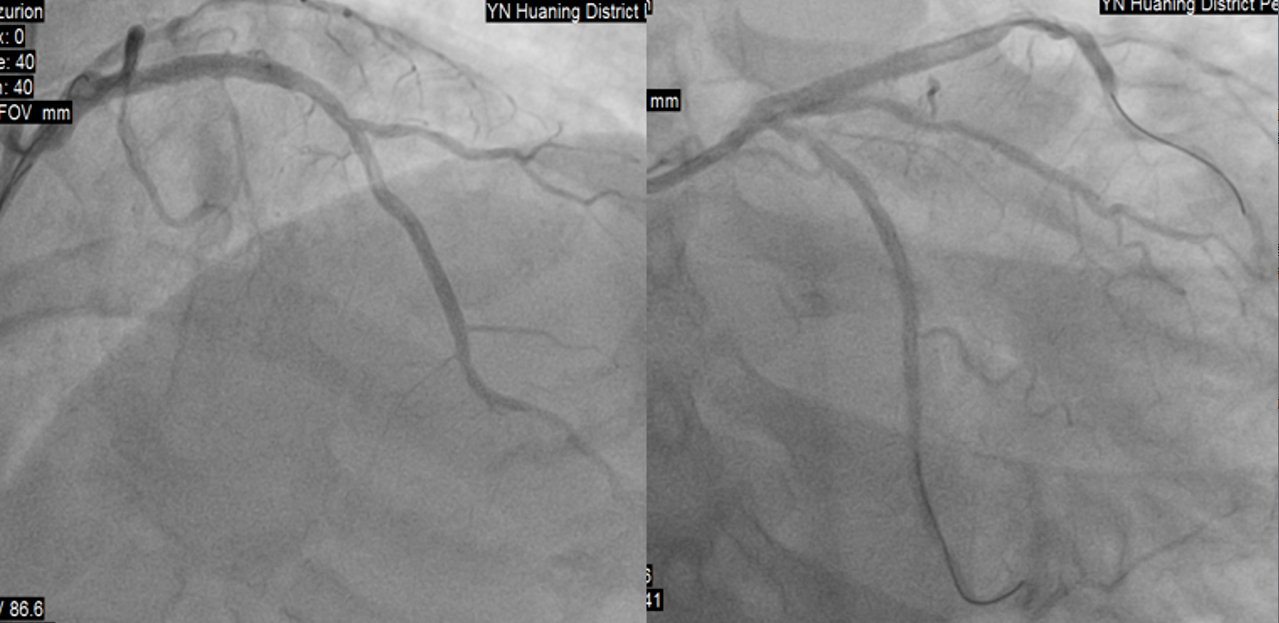

虽然患者胸痛明显缓解,考虑到梗死面积大,于11:20送达导管室,冠脉造影示:均势型,右冠全程弥漫性病变,最狭窄处50%,中段囊性扩张,血流3级;左主干未见明显异常;前降支近段次全闭塞,血流3级;回旋支中段次全闭塞,血流3级。

造影显示溶栓再通,12:20完成前降支、回旋支PCI手术。